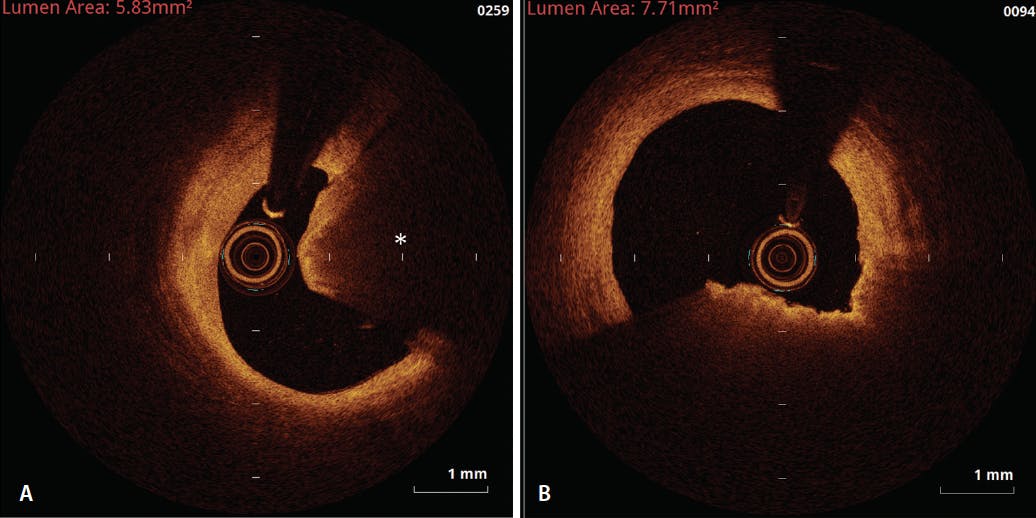

A calcium nodule is defined as an eruptive accumulation of nodular calcification protruding into the lumen.17 Calcium nodules are often underrecognized, as they cannot be appreciated by angiography. However, calcified nodules are not an uncommon entity, and are seen in as many as 6% of cases and over 48% of calcified lesions.18,19 It is important to detect calcium nodules prior to stent implantation because they do not behave similarly to severe concentric CAC. Treatment of calcified nodules with other adjunctive lesion preparation modalities, including rotational atherectomy, intravascular lithotripsy, and specialty balloons is not ideal due to the eccentric protruding nature of these nodules. Orbital atherectomy uniquely allows for significant plaque modification of calcified nodules with debulking of the nodule with lumen enlargement (Figure 3).

Figure 3. Baseline OCT demonstrating a protruding calcified nodule (*) (A). OCT after lesion preparation with orbital atherectomy demonstrates reduction in the nodule size with enlargement of the lumen area (B).